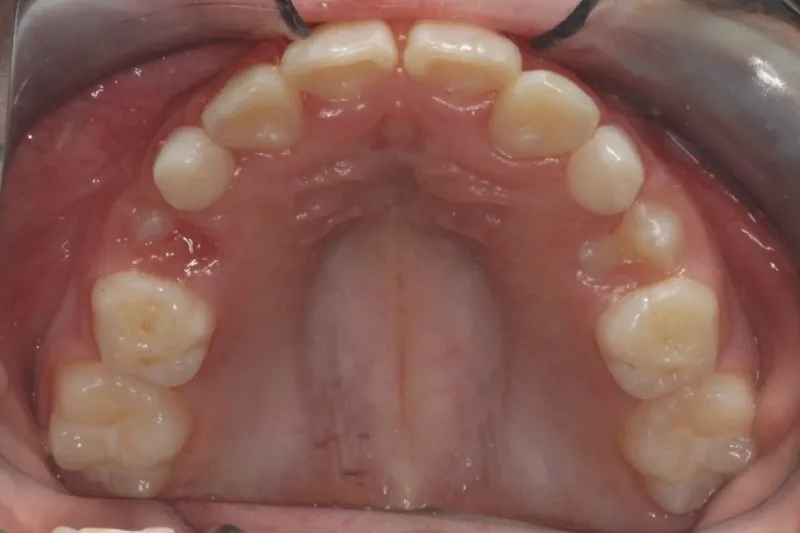

Case Study #1: Severe Crowding

Problem: Top and bottom crowding. The back teeth do not fit together well.

Treatment: An expander to make more space for teeth, followed by upper and lower braces for 22 months.